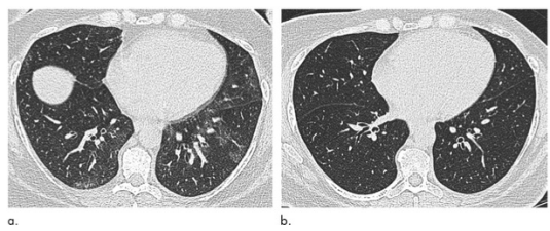

图1 51岁女性,(a)减肥手术前和(b)减肥31 kg后6个月(体重指数下降36.1%)肺部轴位平扫CT图像。术前可见的“马赛克征”在术后消失。